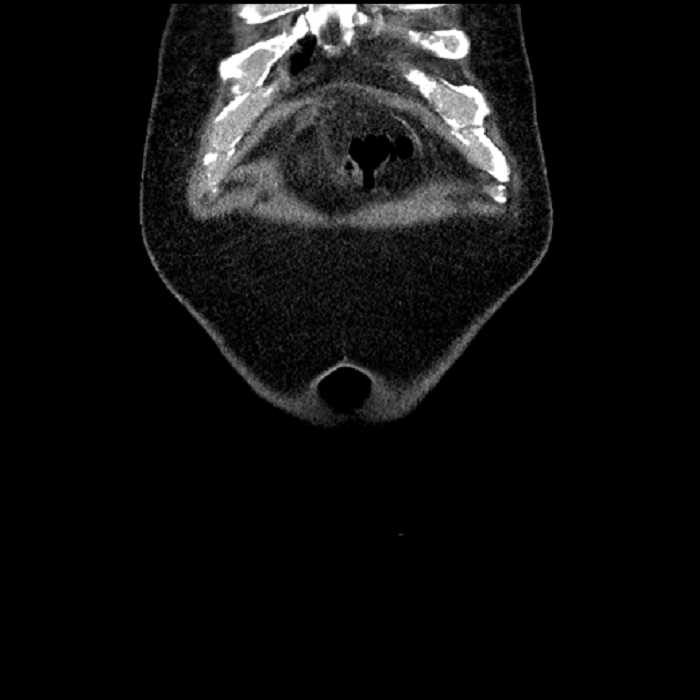

Age: 63

Sex: Male

Indication: Abdominal pain

Acute sigmoid diverticulitis complicated by a small contained perforation and a large abscess in the right hepatic lobe. Additional small subcapsular abscesses along the anterior margin of the left hepatic lobe.

Additionally, loss of the normal fat plane between the peridiverticular collection and adjacent thickened loops of small bowel raises the potential for an enterocolonic fistula.

Hepatic abscess showing the double target sign with low density internally surrounded by a thin inner enhancing rim (red arrow) and ill-defined outer low density rim (yellow arrow). Blue arrow indicates an internal septation. Red arrows: additional smaller subcapsular abscesses. Red arrow: focal contained perforation associated with diverticulitis.